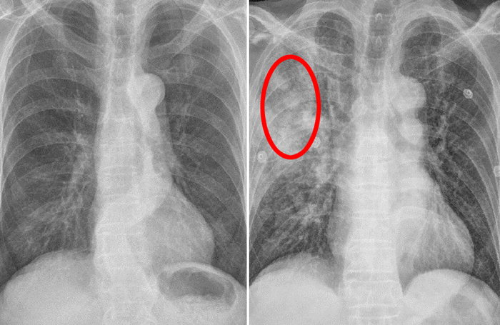

1. 흉부 X-ray 촬영

폐암 검사방법 중 가장 일반적인 검사의 하나로 엑스레이 촬영이 있습니다. 가장 기초적인 검사이고 가장 빠르기도 합니다. 하지만 이 방법은 폐암 세포가 5mm 이상 자란 상태에서 발견할 수 있습니다. 때문에 극 초기의 경우에는 발견하기가 어렵다고 합니다. 또한 흉부 X-ray 촬영은 심장 주변부나 뼈와 겹치는 부분은 확인이 어려울 수 있습니다.